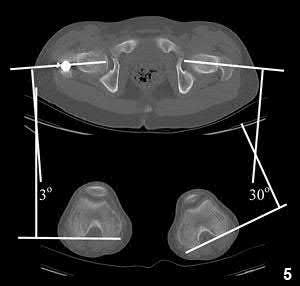

A 13-year-old obese male complains of left knee pain and a limp for 3 weeks. Radiographs are provided:

He is able to bear weight with crutches. During physical examination, as the affected hip is passively flexed, into which position will the limb obligately deviate?

Explanation

In slipped capital femoral epiphysis (SCFE), the proximal femoral epiphysis displaces posteriorly and inferiorly relative to the femoral neck. This altered anatomy leads to an obligate external rotation of the thigh during passive hip flexion, a classic physical examination finding.